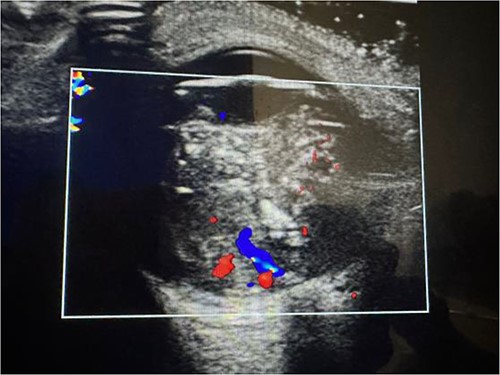

An orbital ultrasound and MRI for a radiological diagnosis, as well as a laboratory examination for a complete blood count (CBC) and full biochemistry (FB), were requested.

The laboratory examination’s results revealed a low hematocrit of 27 and a low hemoglobin (HB) of 8.5 mg/dl. Orbital ultrasonography revealed a hyper-echogenic tumor in the left eye with vitreous seeding (Fig. 2), while the orbital MRI showed a left intraocular mass of 10.10 mm by 8.7 mm with medium intensity in T1W/FLAIR sequences and a low intensity in T2W images (Fig. 3). The lesion has a slightly heterogeneous contrast enhancement in the post-contrast sequence with group D international classification of Rb (ICOF) stage I. The radiological findings most likely indicated Rb. Tumors occupied 50% of the globe, but there was no subretinal detachment. Fortunately, the tumor has not affected the optic nerve. An enucleation procedure (removal of the whole contents of the eye) under general anesthesia was performed (Fig. 4). Histopathological examination showed hyperchromatic small round blue cells with scant cytoplasm arranged in sheets, nests, and Flexner–Wintersteiner rosettes with histologic G3 with endophylitis, tumor necrosis, and calcification (35% of calcification is eosinophilic) that was consistent with Rb (Fig. 5). After 3 months of follow-up in the outpatient department, a prosthetic eye was implanted for cosmetic purposes (Fig. 6).